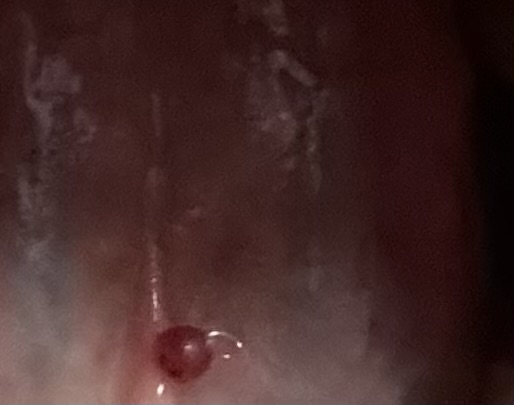

혀 밑쪽에 이상한 돌기가 생겼어요

생긴지는 좀 됐고 작았다가 커졌다가 작았다가 다시 좀 많이 커졌어요 계속 혀로 만지니까 더 커진것같아요

그리고 끝쪽에 여드름처럼 하얀게 있어요